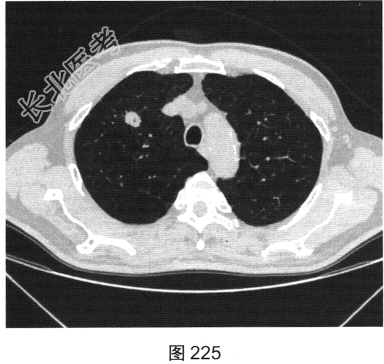

- [材料题] 患者女性,70岁。因“咳嗽、痰中带血3个月余”就诊。听诊无异常发现。胸部正侧位片发现右肺上叶类圆形小结节。

- 多项选择题2.[提示]患者行胸部CT检查,如图225、图226所示。该患者CT图像可见的阳性表现为( )

A、软组织密度结节

B、支气管充气征

C、毛刺征

D、空泡征

E、分叶征

F、棘状突起